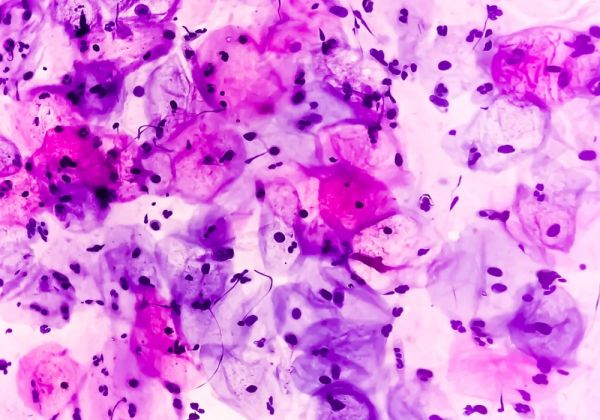

常用的细胞学筛查手段分为两种:巴氏涂片和TCT检查。巴氏涂片(Pap smear)即宫颈脱落细胞涂片,是将从子宫颈部刮取的少量上皮细胞,涂抹到载玻片上,经染色后在显微镜下观察细胞形态是否正常。高危男性群体,例如HIV阳性的男同性恋人群,也建议定期进行肛门巴氏涂片筛查。巴氏涂片简单而便宜,被广泛应用于普查,但缺点是标本中上皮细胞常堆叠在一起,影响观察,因而准确率不足。

图4. 显微镜下的宫颈鳞状上皮细胞。| 图源:https://www.the-scientist.com/news-opinion/why-some-hpv-infections-carry-more-cervical-cancer-risk-70931

TCT(Thinprep cytological test)检查的全名为“薄层液基细胞学检测”。细胞经固定、离心、制片、染色等多个步骤,可以获得更加清晰的图像。TCT准确率较高,但依赖专业的设备仪器,成本较高,因此一般建议在巴氏涂片中发现异常细胞的患者,应在一个月以后再行TCT检查。